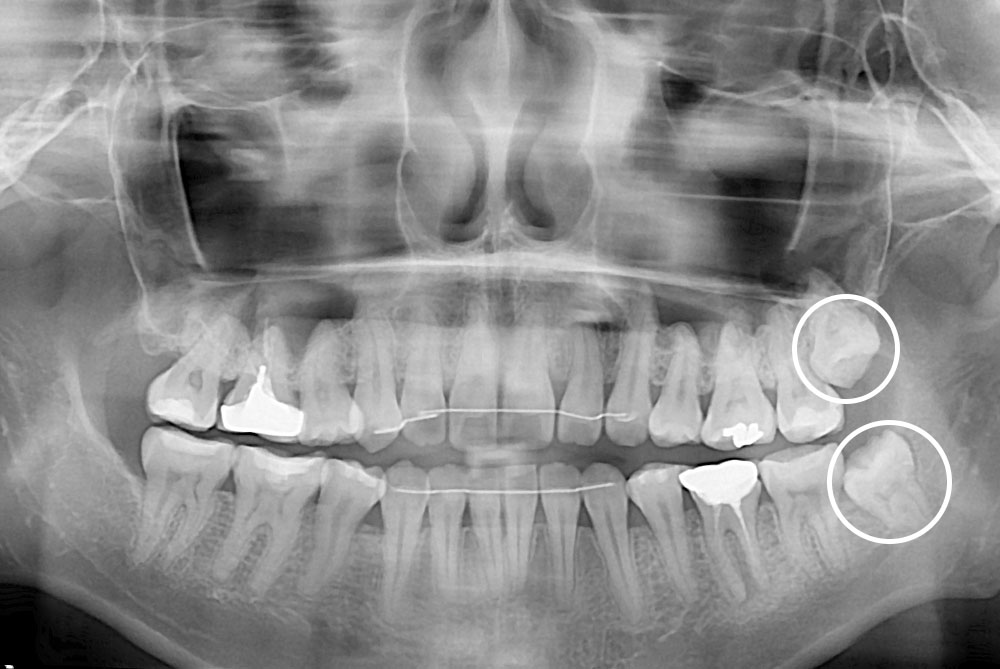

[사랑니] 매복 사랑니 발치

치료전 : 2019-10-02